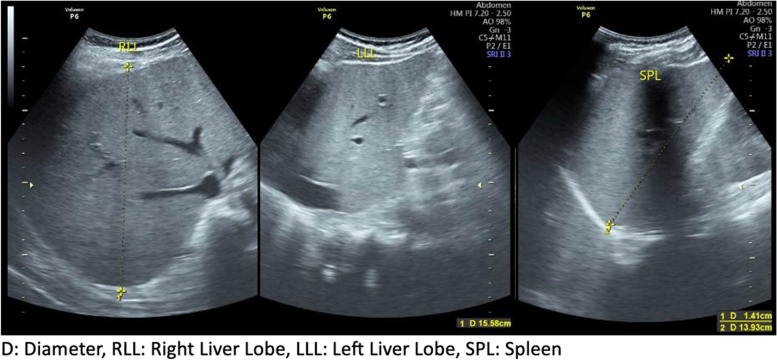

Case presentation: A 46-year-old man was brought to the Emergency Room (ER) because of fever and chills for 6 days. Complaints were accompanied by nausea and vomiting three times a day. The patient also experienced headaches, weakness, coughing, and a runny nose after two days of admission. The patient had no history of traveling from a malaria-endemic area. The patient was transferred from the Emergency Department (ED) to the High Care Unit (HCU), and during 1 day of intensive care at the HCU, there was a clinical deterioration characterized by dyspnea, icteric sclerae, acral edema, tenderness in both calves, and rash in the abdominal area. Due to worsening respiratory function, the patient was placed on a ventilator. During intensive treatment, the patient continued to show deterioration. The clinical findings suggested a possible feature of Weil's disease or fulminant hepatitis, and although the patient was in intensive care, there was no clinically significant improvement. Furthermore, microscopic blood smear examination and rapid diagnostic tests (RDTs) for malaria were carried out on the 4th day of treatment with negative results. As there was no clinically significant improvement, it was decided to take a blood smear and repeat RDT on the twelfth day, which showed a positive result for falciparum malaria. Subsequently, artesunate was administered intravenously, and the patient's condition began to improve with a negative parasite count the following day. The patient was discharged in good clinical condition on day 25 of treatment.